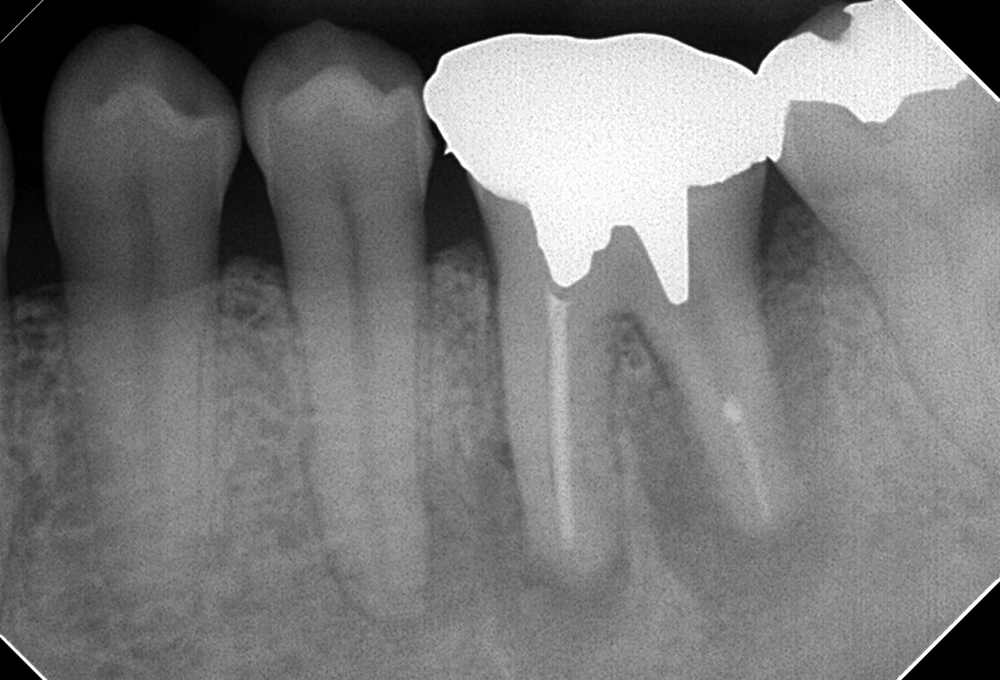

①術前 下顎大臼歯近心根破折ファイル有

③破折ファイル除去後

④根管充填